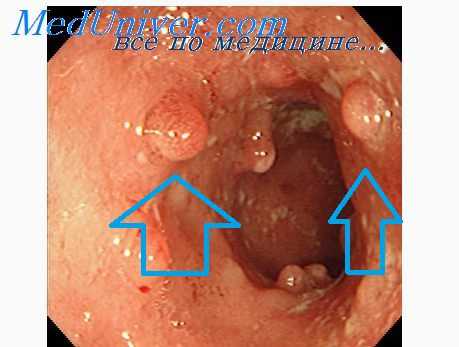

Электрокоагуляция применяется при единичных и множественных полипах, расположенных в пределах досягаемости для осмотра и воздействия через ректороманоскоп, т. е. на глубине до 30 см. Пассивный широкий электрод электрокаутера прибинтовывают на ноге через увлажненную физиологическим раствором салфетку. Активный электрод вводят через ректороманоскоп, покрытый изнутри изолирующей электрический ток пластмассой.

Под контролем зрения электрокоагулируется каждый видимый полип. При этом нужно проявлять осторожность и прижигание производить от вершины полипа к основанию, а не наоборот. Известны наблюдения, когда настойчивое отжигание полипа от основания приводило к перфорации кишечной стенки непосредственно во время процедуры или через несколько дней, в период отторжения некротических тканей.

Такие полипы, доступные осмотру через ректороманоскоп, можно с успехом лечить следующим комбинированным способом. Один, два и даже три раза в неделю производится кускование полипа щипцами через тубус ректороманоскопа. Кускование производится до тех пор, пока поле зрения не зальет кровью. Дальнейшее откусывание кусочков опухоли становится невозможным. В это время на конец ватодержателя навертывают ватку, опускают в зеленую массу провернутого чистотела и пропитывают этой массой. Некоторая часть массы остается на ватном тампоне. Через тубус ректороманоскопа ватный тампон с зеленой массой чистотела подводят к кровоточащему участку полипа и прижимают на 5—10 минут.

Показанными для лечения клизмами с чистотелом являются истинные, доброкачественные, аденоматозные, единичные или множественные полипы толстой кишки, располагающиеся на узкой ножке. Аденоматозные полипы, имеющие широкое основание, и небольшие виллезные опухоли, находящиеся в пределах доступности для осмотра через ректороманоскоп, также можно с успехом лечить чистотелом с одновременным кускованием их щипцами. У детей после удаления одиночных полипов пальцем по Мангейму или скусывающими щипцами следует сделать 5—6, до 10 лечебных клизм с чистотелом с целью профилактики рецидива.

Трудно точно определить количество полипов при ректороманоскопии, особенно при тотальном полипозе, когда невозможно видеть нормальную слизистую оболочку или если полипы ветвисты, разных размеров, прикрывают один другой, а в особенности при большом количестве слизи, когда они покрыты слизистыми наслоениями. Но общее впечатление о количестве и качестве полипов у данного больного остается в памяти у врача и фиксируется описанием в истории болезни.